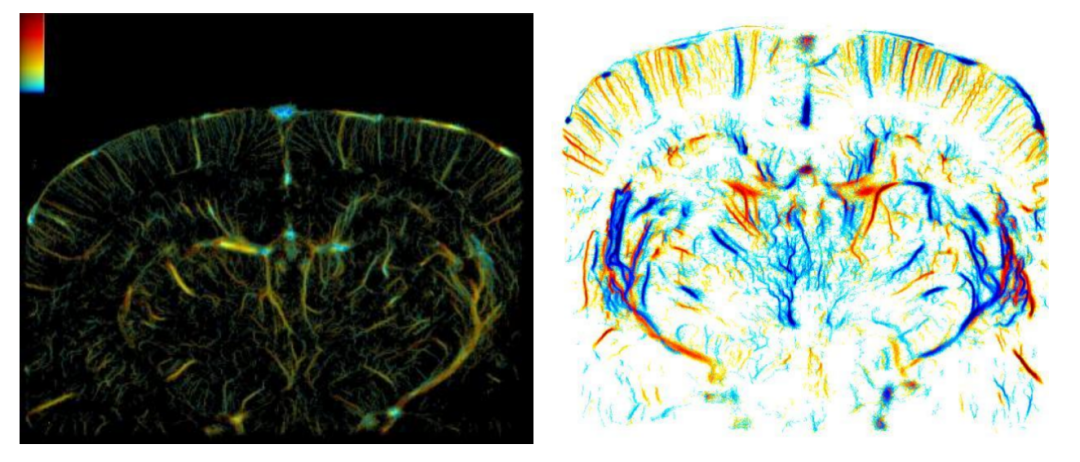

传统超声受限于波长,难以捕捉直径小于100微米的血管。玉研Sonorover超分辨率成像系统借助强大的图像处理能力使系统具备卓越的超高分辨率超声成像性能,能够清晰呈现微小组织结构和精细解剖细节,助力精准成像。

不同于fMRI的分钟级延迟,玉研Sonorover超分辨率成像系统fUS技术以每秒100帧的速度捕捉脑血流动态变化。fUS脑功能超声成像通过超快超声和超灵敏血流成像技术,获取脑部组织微小血流变化,根据神经血管耦合机制,可实时获取脑功能活动状态。

大鼠脑血流超分辨率成像,精确观察脑部血流动态,实时生理状态监测。

脑疾病模型评估,观察中风、阿尔兹海默病等病变区域微血流异常,监测疾病进展与治疗反应。

采用周期性刺激大鼠胡须实验,获取大鼠脑区(S1BF)血容量的变化量与触觉刺激的对应关系。

fUS脑功能成像用于追踪清醒大鼠的癫痫发作过程。